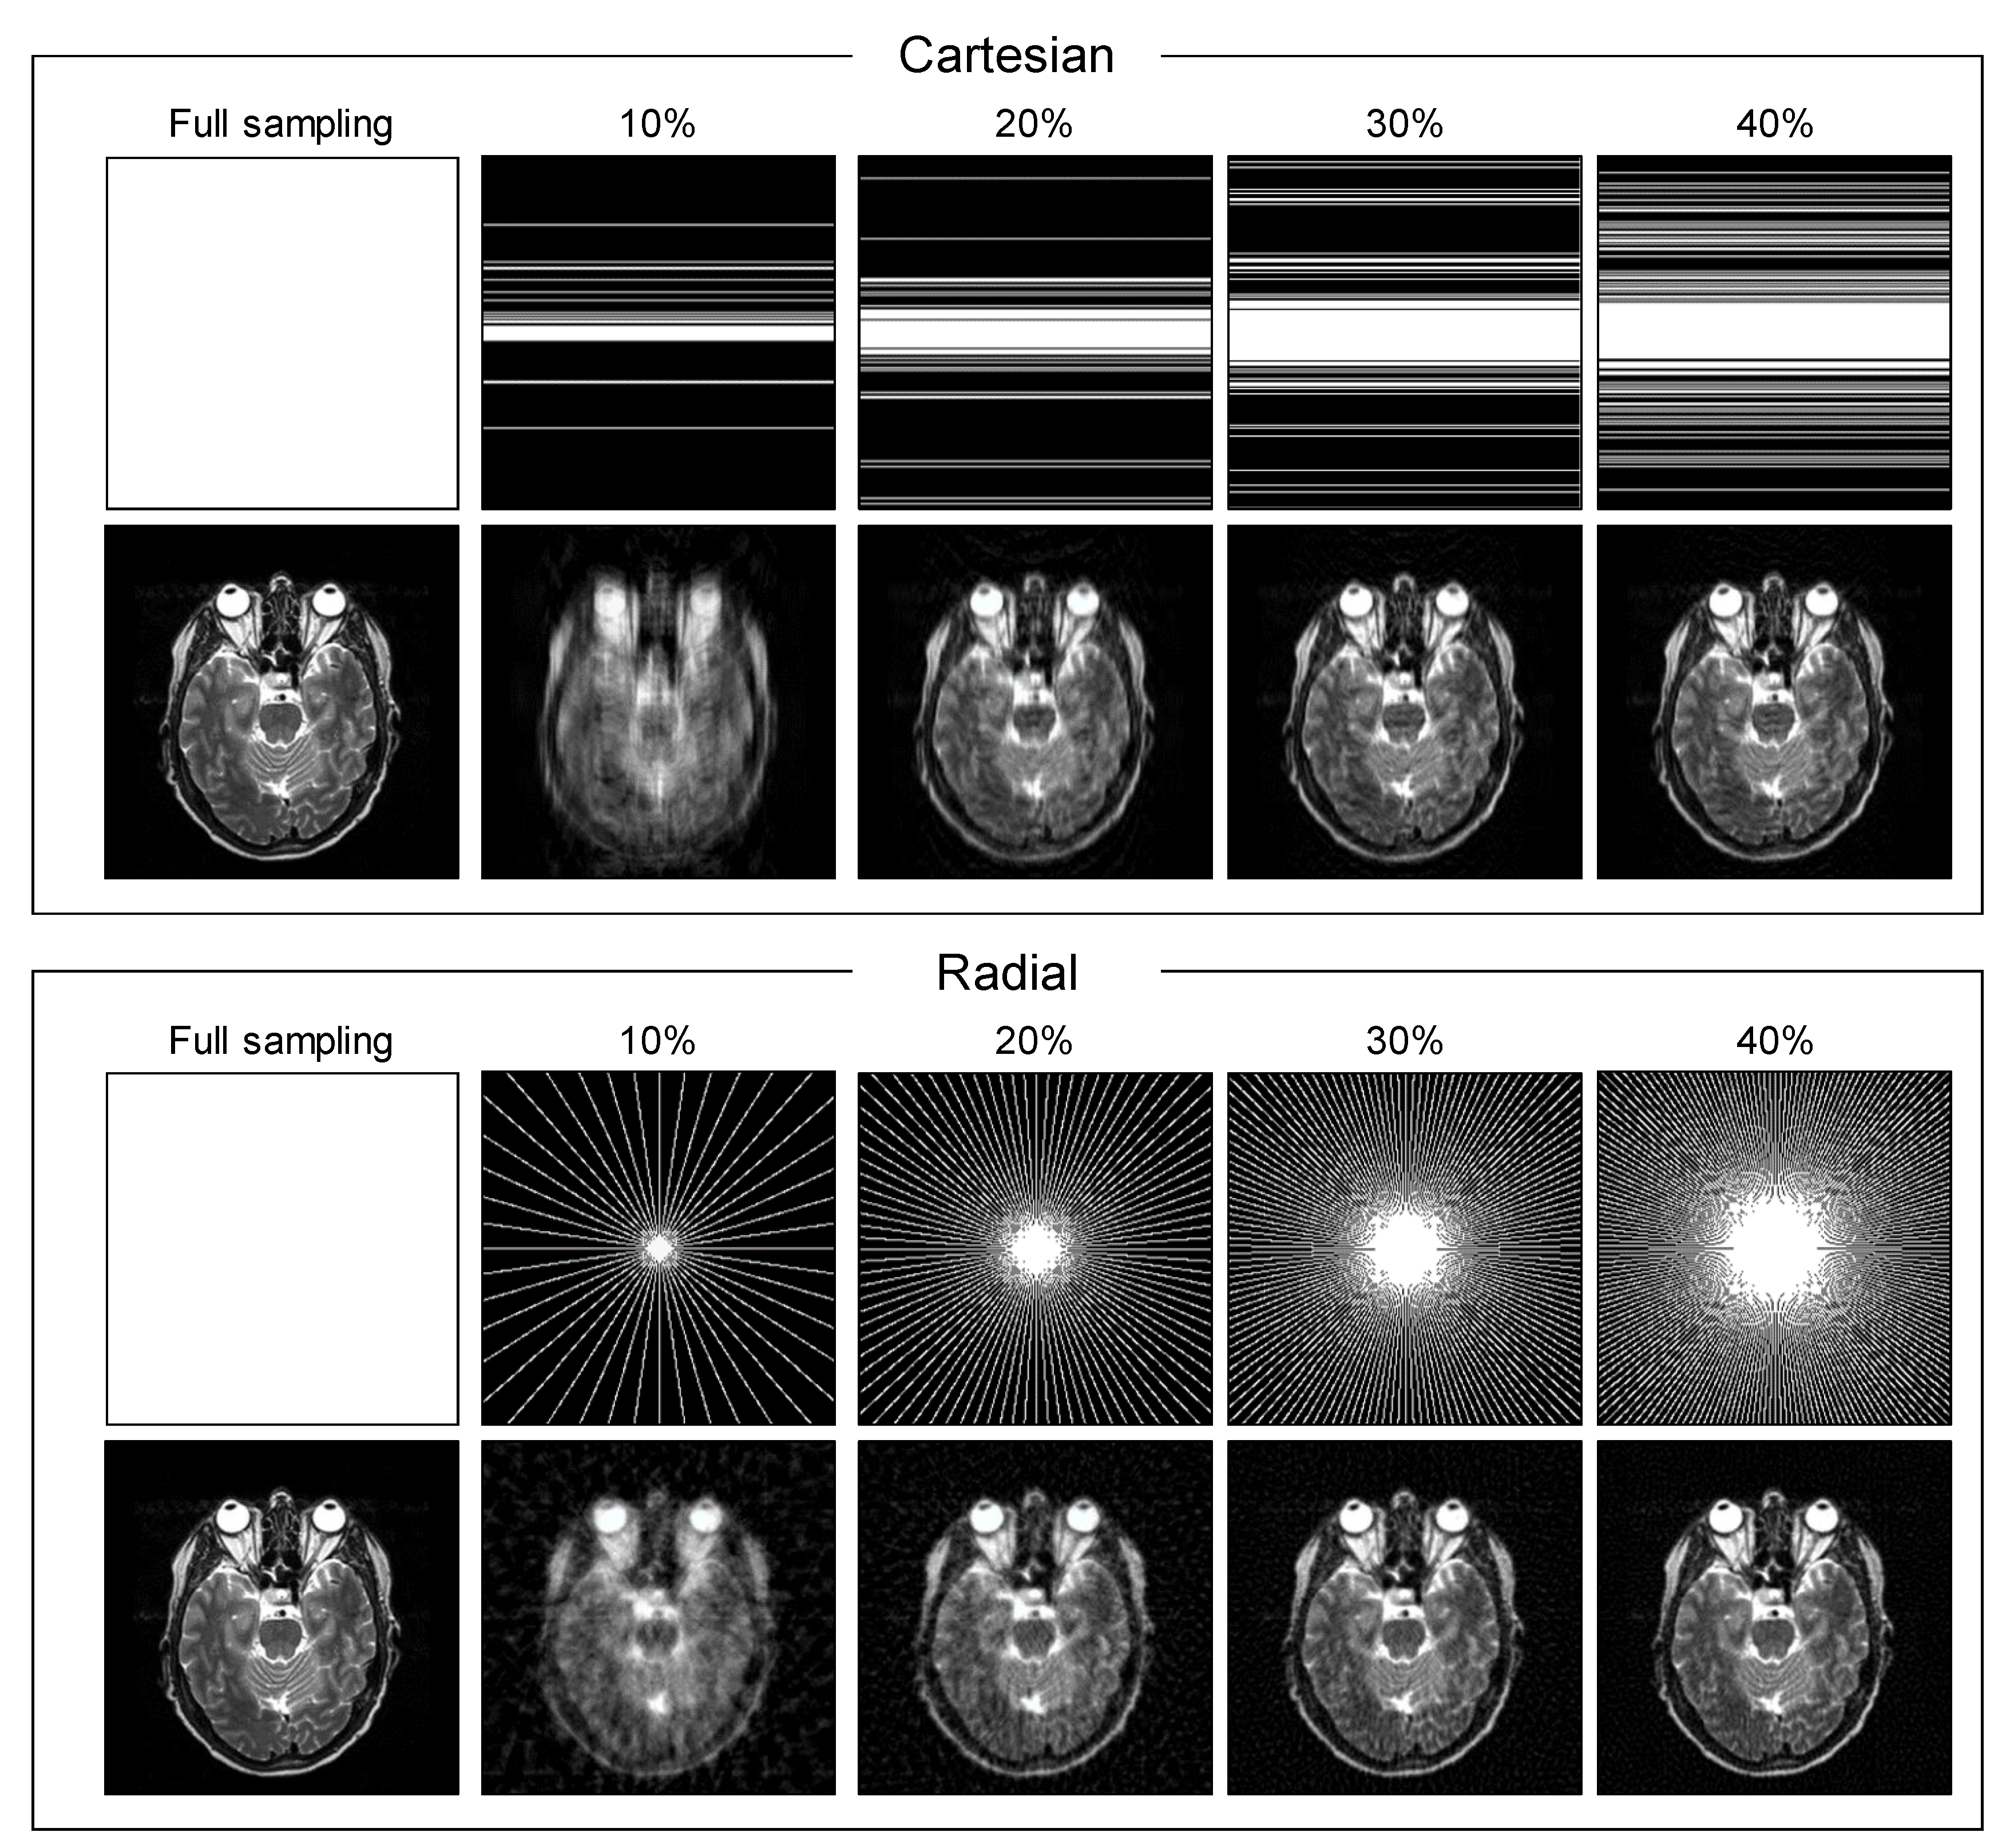

2.3. Experimental Setup

3. Results